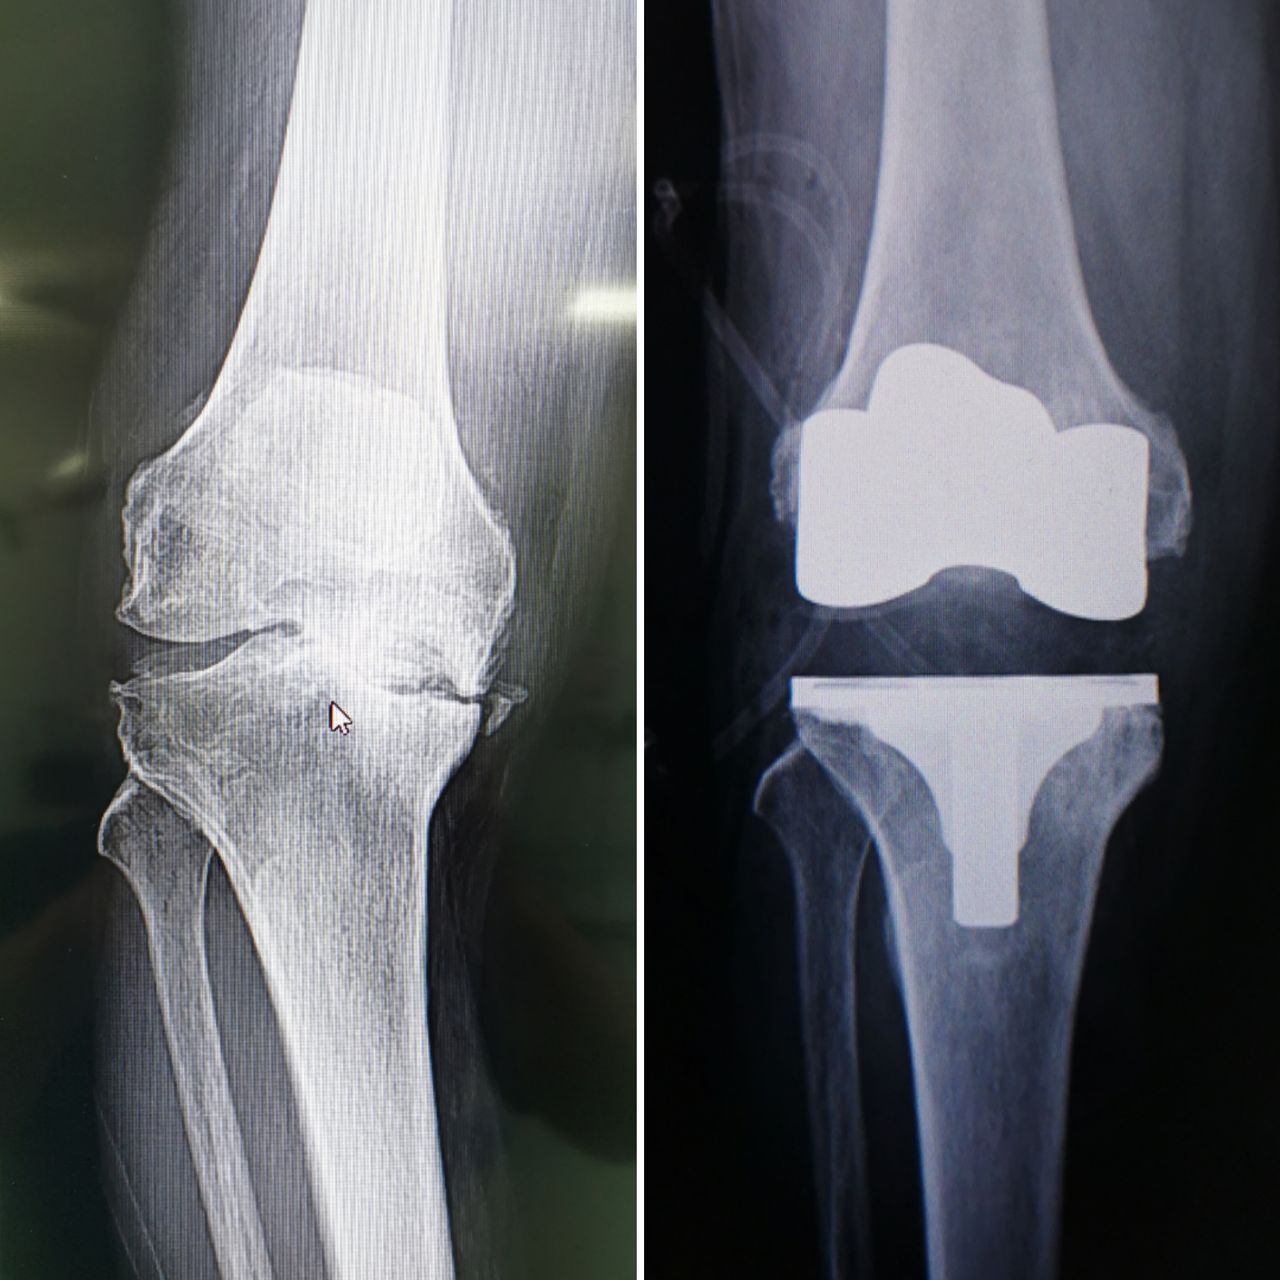

2. ALTA ESPECIALIDAD EN REEMPLAZOS ARTICULARES (PROTESIS DE CADERA, RODILLA Y HOMBRO)

• Prótesis de rodilla